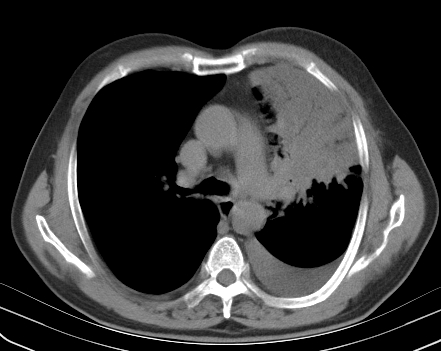

以下是引用老爱克斯新网客在2008-7-31 6:30:00的发言:[br]左肺上叶大片状病灶,左肺上叶支气管狭窄呈鼠尾状,左肺门增大,纵隔内见肿大淋巴结,左侧胸腔积液,余肺清晰。左肺中心型肺癌淋巴结转移,

以下是引用zjb在2008-7-31 6:32:00的发言:[br]左侧中心性肺癌 阻塞性肺炎 肺不张 胸腔积液 建议气管镜

以下是引用zjzjr在2008-7-31 8:45:00的发言:[br]考虑左侧中心性肺癌伴阻塞性肺炎,左肺上叶肺不张,纵隔淋巴结转移;左侧胸腔积液。建议行纤支镜检查。

以下是引用sdzyy在2008-7-31 8:47:00的发言:[br]病灶较治疗前有所进展,胸水增多, 左侧中心性肺癌 并 阻塞性肺炎 肺不张 胸腔积液 可能性大; 建议气管镜检查。 [br] [br]